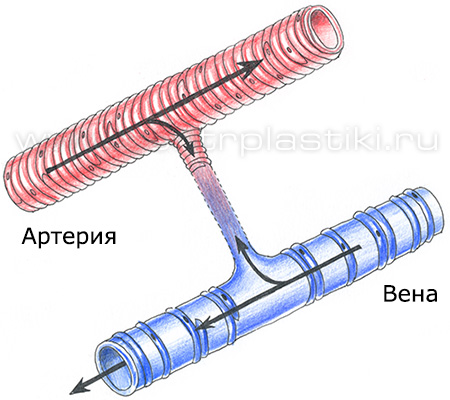

Варикоз - причины и механизмы развитияВарикозная болезнь – это полиэтиологическое заболевание, часто возникающее из-за генетической предрасположенности (так называемая слабость соединительной ткани), гормонального влияния (беременность, прием гормональных препаратов), конституции тела (чаще заболевают люди высокого роста и те, чья масса тела превышает норму), расовой принадлежности (например, варикозом редко страдают люди желтой и черной расы).  На возникновение заболевания существенно влияют образ жизни и характер трудовой деятельности («стоячая» работа, тяжелые физические нагрузки, частое ношение высоких каблуков).  Все этиологические факторы варикоза условно делятся на две группы: предрасполагающие и производящие. Предрасполагающими факторами называют те, что влияют на морфологические и функциональные изменения стенок поверхностных вен и клапанов. Эти факторы сами по себе не приводят к расширению вен, но создают условия, в которых образуется анатомическая и функциональная неполноценность системы поверхностных вен ног.  Производящие факторы представляют собой многочисленную группу, и среди них выделяют три ведущих механизма, ответственных за венозную гипертензию нижних конечностей: 1. Нарушение оттока крови из венозной системы нижних конечностей (из-за высокого роста, статической нагрузки, внутрибрюшного давления, кашля, запора, беременности). 2. Переход крови из глубоких вен в поверхностные приводит к расширению глубоких вен, что влечет за собой относительную клапанную недостаточность и варикоз поверхностных вен. 3. Переход крови из системы артериального кровотока в поверхностные вены по артериовенозным коммуникациям, которые в нормальном состоянии не функционируют, а служат лишь для ситуаций тяжелой мышечной работы, действия высокой температуры, и т.д.). В настоящее время механизмы повреждения стенок вен при варикозе объясняются при помощи феномена лейкоцитарной агрессии. При гипертензии нормальная вена, которая обладает значительным резервом возможностей, реагирует на изменение ситуации повышением своего тонуса. Если же возникла врожденная или приобретенная слабость венозной стенки и просвет вены необратимо увеличился, то этого не происходит. Современные представления о механизмах повреждения стенки вены при варикозной болезни основываются на феномене лейкоцитарной агрессии. Нормальная вена, обладая значительными резервными возможностями, реагирует на гипертензию повышением своего тонуса. Этого не происходит при врожденной или приобретенной слабости мышечно-эластических образований венозной стенки, когда в ответ на периодическое или постоянное повышение внутрисосудистого давления постепенно развивается необратимое увеличение просвета вены.  1 - Макрофаг; 2 - Миграция и адгезия макрофага; 3 - Клапанный синус; 4 - Молекулярная экспрессия; 5 - Проксимальный отдел вены; 6 - Нижняя поверхность створки клапана; 7 - Венозный клапан; 8 - Дистальный отдел вены; 9 - Венозная стенка. Замедление кровотока приводит к краевому стоянию лейкоцитов, которое происходит из-за их плотного контакта с эндотелийным слоем, на поверхности которого начинают экспрессироваться адгезивные молекулы, деятельность которых стимулируется медиаторами воспаления. В результате образуется хронический процесс воспаления, к которому присоединяется патогенная микрофлора и развитие инфекции. Стенка варикозной вены теряет тканевый активатор плазминоген, это снижает местную фибринолитическую активность, возрастает риск спонтанного тромбообразования и развития острого варикотромбофлебита. Повышается проницаемость капиллярной системы и внутрикапиллярное давление, это приводит к просачиванию из сосудистого русла в ткани не только воды, электролитов, и различных белковых фракций, но и форменных элементов крови. Геморрагическое пропитывание усиливает склеротические процессы в тканях и служит причиной возникновения характерной гиперпигментации кожи.  Флебостаз усиливает сопротивление венозного конца капиллярного русла, лимфатические капилляры перегружаются, происходит расширение лимфатических сосудов, объем оттекающей лимфы увеличивается. Лимфатическая система оказывается неспособна к достаточному дополнительному дренажу из тканей пораженной конечности: развивается отек, а белки плазмы и лейкоциты проникают в околососудистые ткани. Возникает процесс полимеризации фибриногена вокруг капилляров, происходит возникновение периваскулярных фибриновых муфт, которые ещё больше нарушают трофику и способствуют развитию язв. Местные медиаторы воспаления провоцируют появление разнообразных аутоаллергических реакций, которые провоцируют склерозирующий лимфангоит. Сосуды лимфы перестают ритмически сокращаться и становятся неподвижными трубками. Стенки сосудов становятся более проницаемыми, сквозь них в окружающие ткани просачивается богатая белками лимфа, развивается фиброз. Отек становится все более и более стойким и может превратиться во флебогенную слоновость. Также нарушается центральная гемодинамика, поскольку в варикозно-деформированных венах содержится от 1,5 до 3-х литров крови. Это ведет возникновения компенсаторного увеличения ОЦК (гиперволемии) и перегрузке венозного русла. Миокард изменяет свое функционирование, поскольку при ортостазе, если снижается сердечный индекс, то отсутствует компенсация его тахикардией, а это ведет за собой недостаточность системного кровообращения. При отсутствии лечения варикоз переходит в стадию трофических изменений мягких тканей ног вплоть до образования трофических язв. |